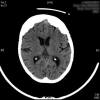

Higroma frontal bilateral